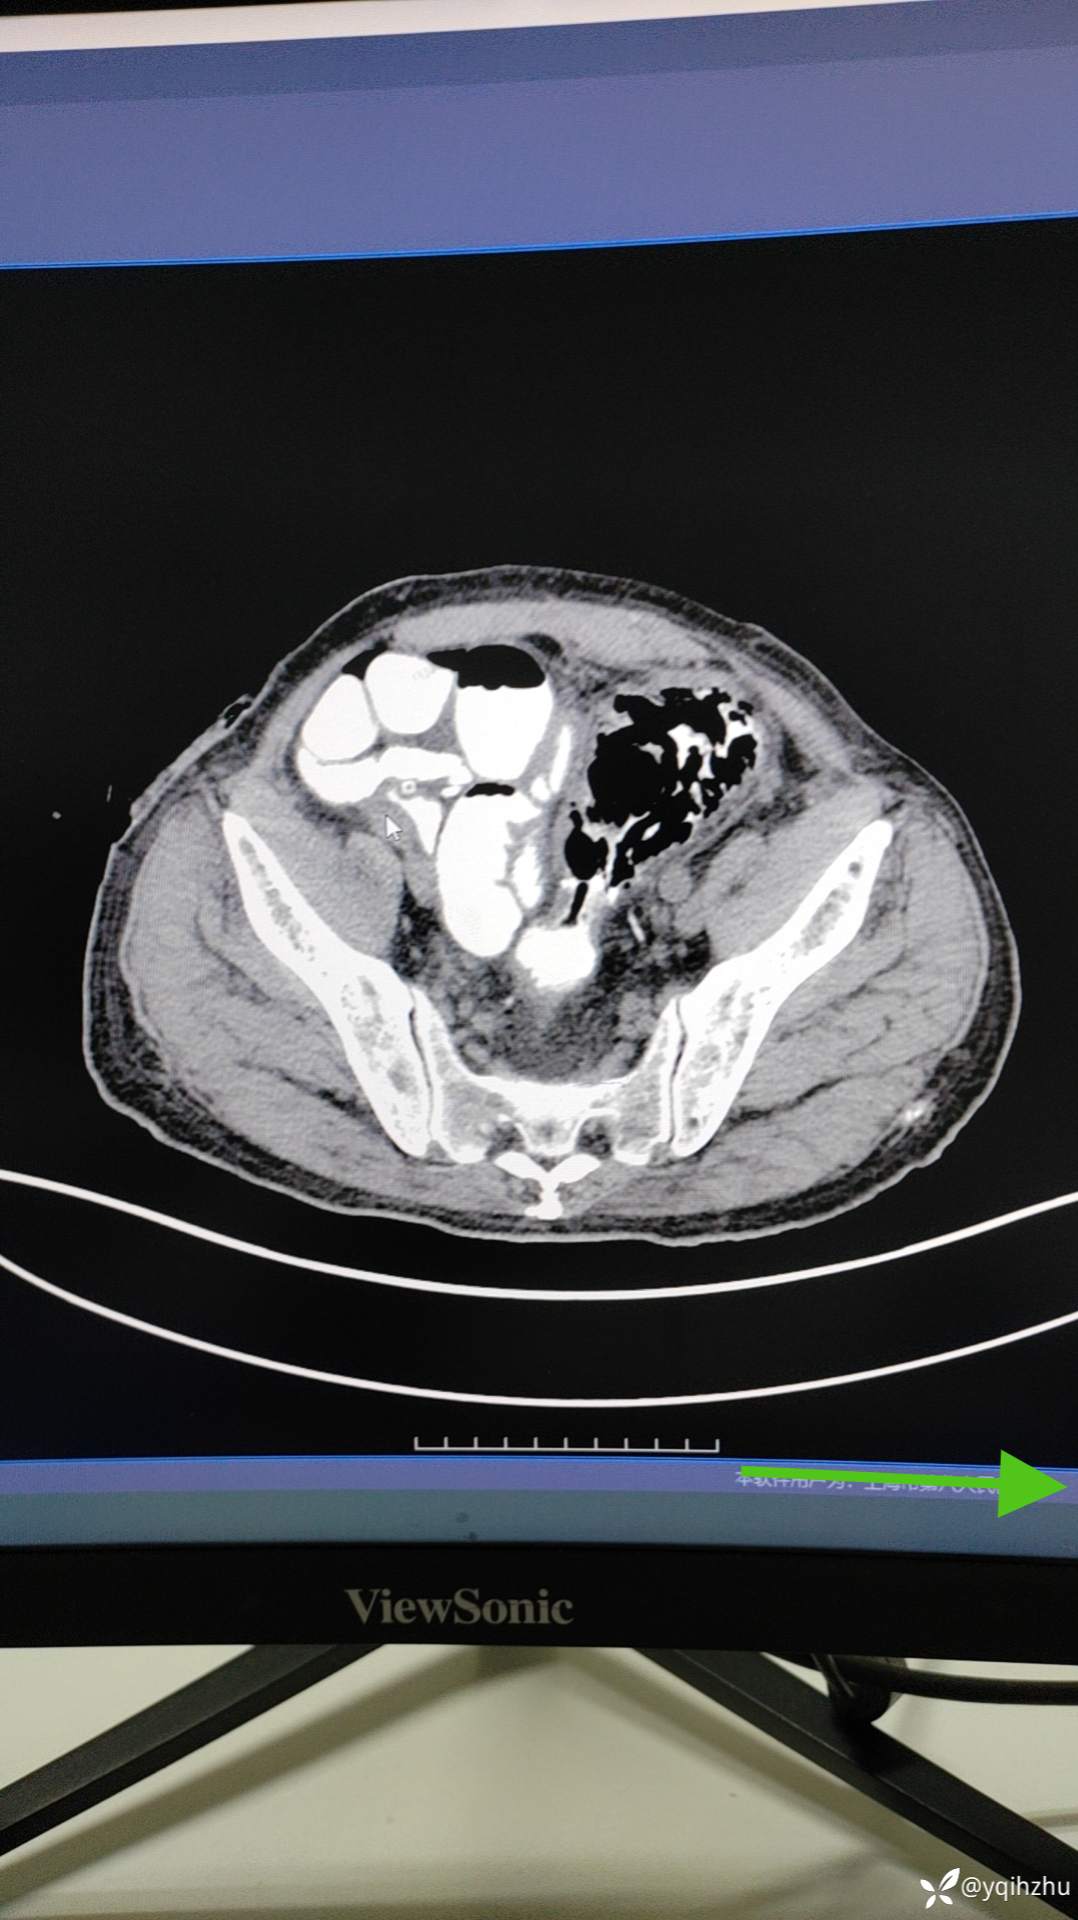

患者老年男性,82岁,急性肠梗阻入院,当时急诊行肠镜下支架植入术,术后3周在全麻下行腔镜下乙状结肠癌根治术,手术顺利,术中见乙状结肠和直肠肠管无明显水肿,给于一期切除,吻合口吻合器切除+浆肌层保埋,骶前部置双套管引流。术后第3天解便和排气,给于饮水,但2小时后出现腹胀不适,给于禁食,胃肠减压,等营养保守治疗,目前术后第15天,给于碘海醇口服后6小时造影。图片如下